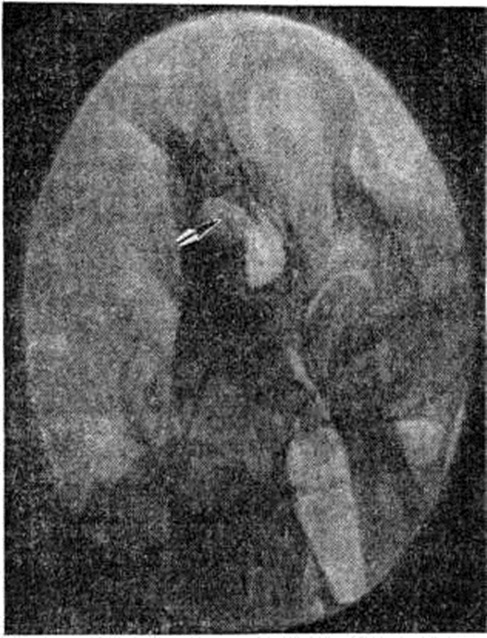

Важное диагностическое значение в сочетании с клинические, данными имеет рентгенологическое исследование. Рентгенографию височной кости производят в специальных проекциях (смотри полный свод знаний: Среднее ухо). Ценные дополнительные сведения могут быть получены при томографии височных костей в прямой и боковой проекциях (смотри полный свод знаний: Краниография). Рентгенологические картина зависит от размеров и локализации холестеатомы уха, которая распознается по вторичным признакам — изменениям в прилежащих костных структурах. Небольшие холестеатомы могут не давать рентгенологическое симптоматики. Крупная холестеатома приводит к увеличению размеров сосцевидной пещеры и надбарабанного углубления, истончению и разрушению наружной стенки последнего и входа в сосцевидную пещеру. Контуры дефекта кости, образованного неосложнённой холестеатомой, чёткие, дефект имеет округлую или полигональную форму с небольшой склеротической полоской по периферии (рисунок). Отсутствие чёткой и плотной капсулы холестеатомы является рентгенологическим признаком обострения процесса.